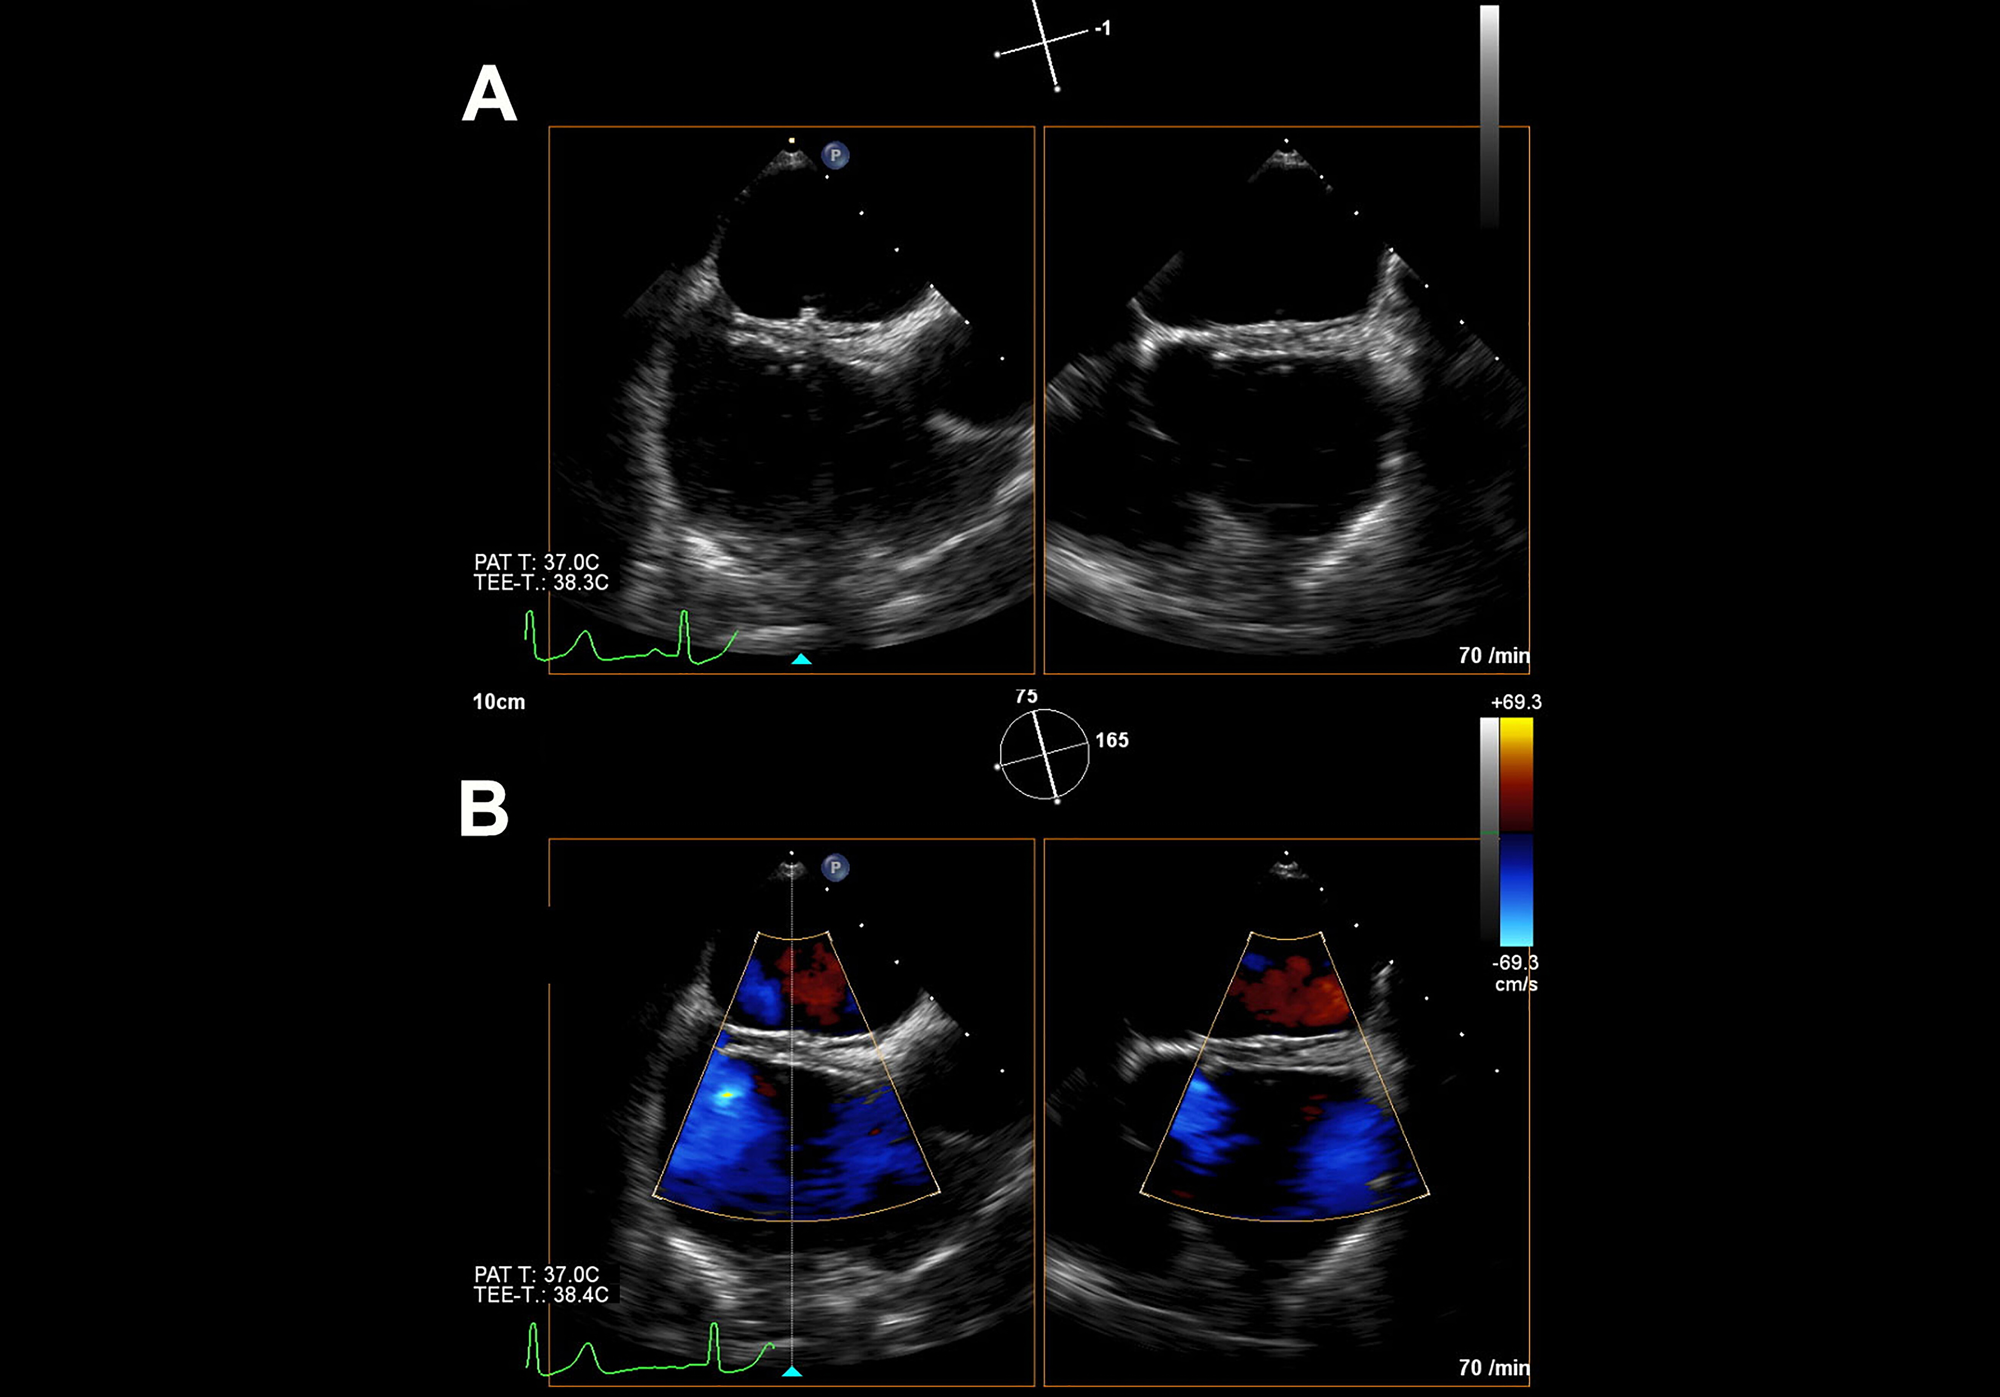

Foramen-ovale-occluder